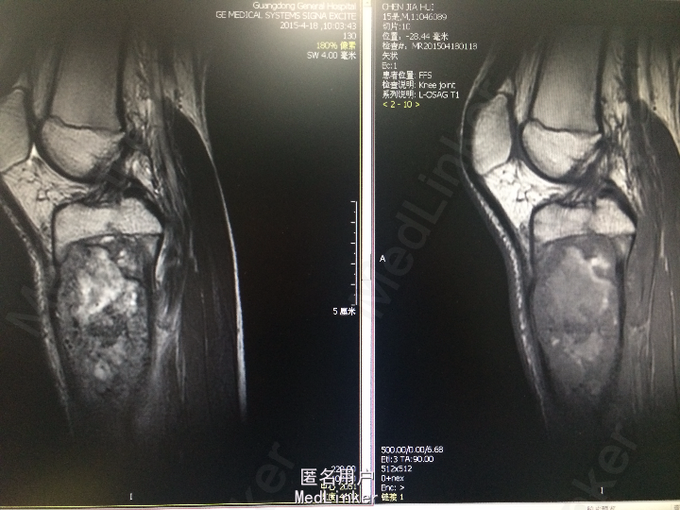

青少年男性 主诉:扭伤左小腿后反复疼痛4月,加重伴肿胀2周。 病史:患者于4月前跳舞时不慎扭伤左小腿上段,后出现左小腿疼痛,呈酸痛性质,呈间歇性,无明显加重及缓解因素,无夜间疼痛加重,无伴发热、盗汗,当时程度较轻,未予重视。2周前患者无明显诱因出现症状加重,并觉左小腿上段肿胀,无局部红肿、发热,无伴关节活动受限,遂于当地医院就诊,查X线提示左胫骨近侧干骺端占位性病变,考虑来源于软骨类肿瘤可能性大。行左小腿MR平扫+增强提示:左侧胫骨上段占位性病变 ,考虑恶性骨肿瘤(骨肉瘤)。现为进一步诊治就诊于我院,患者自起病以来,无发热,无咳嗽、咳痰,大小便正常,体重无明显变化。

诊断:恶性骨肿瘤:骨肉瘤? 处理:完善相关检查,局麻下行左胫骨肿物穿刺活检术,病理诊断为骨肉瘤。遂进行AP方案诱导化疗,其中吡柔比星针(合)40mg d1-2+顺铂针 30mg d1-5,过程顺利。后患者肿瘤疼痛加重,予止痛治疗,住院期间下床时不慎扭伤左下肢后疼痛加重,行左膝关节X光检查提示病灶部位骨折,断段对位对线上课,暂予止痛、夹板固定,择期手术治疗。后行全麻下左大腿截肢术。术后予止痛、补液、预防感染等治疗,患者恢复良好。